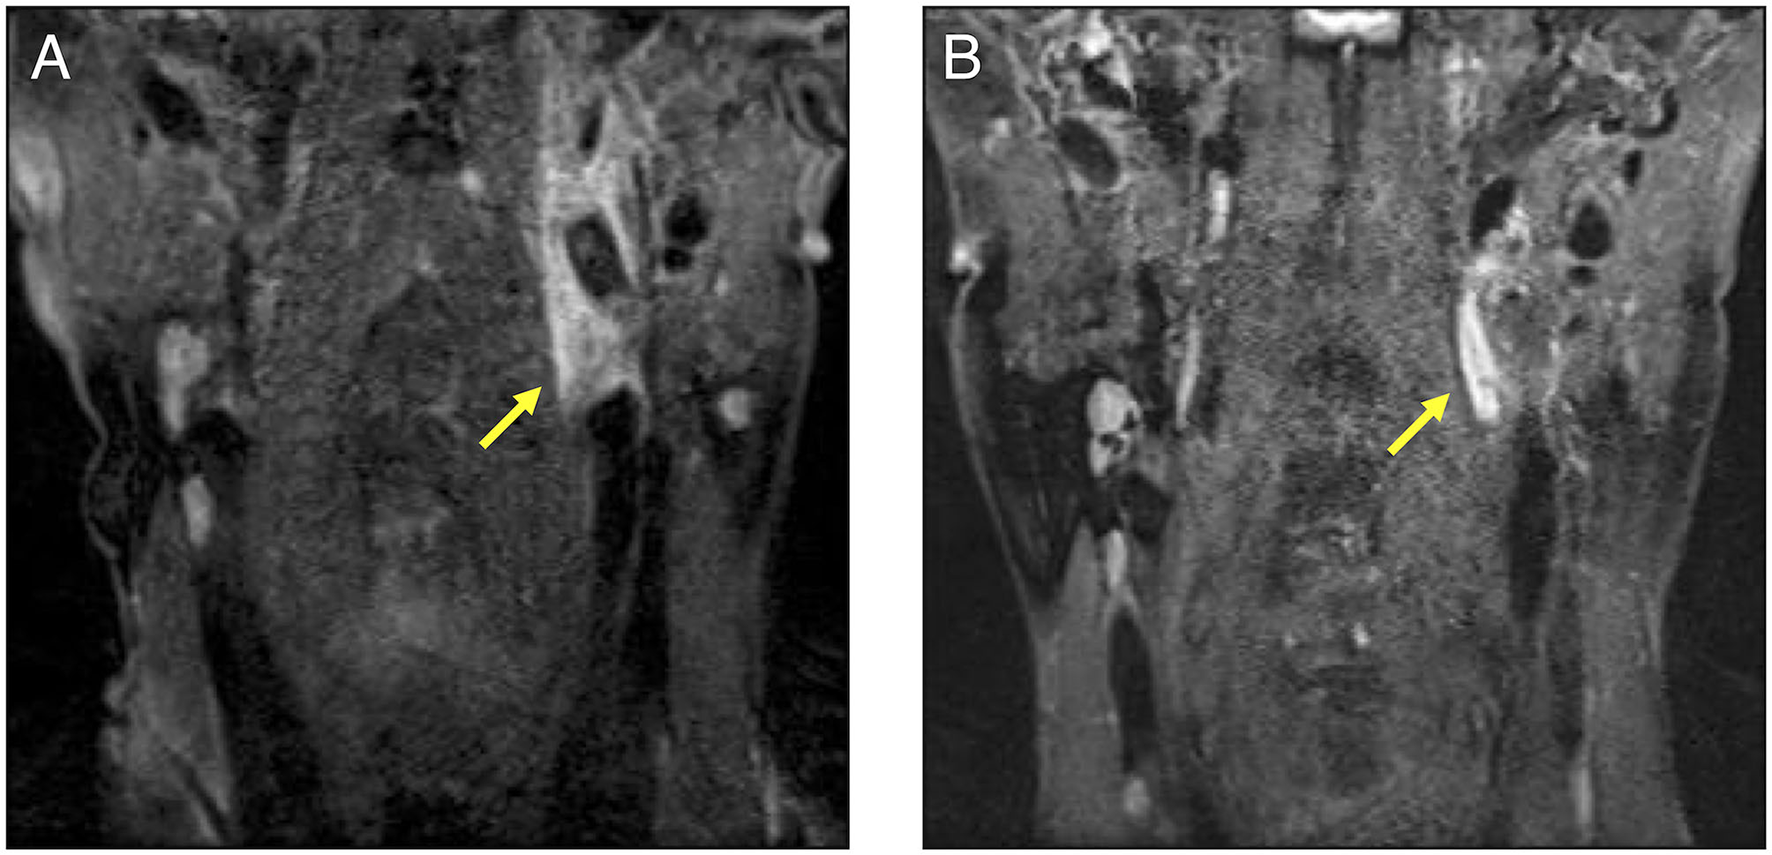

Figure 2

A cervical contrast-enhanced MRI comparison before and after the treatment in our patient. (A): This MRI was performed before treatment. Aneurysm, stenosis, and dissections were observed in the left internal carotid artery indicated by the arrow. A contrast effect was also observed around the lesion. (B): The participant underwent MRI as an outpatient after treatment. The contrast effect around the left internal carotid artery had decreased. MRI, magnetic resonance imaging.

We administered intravenous methylprednisolone (mPSL) [1,000 mg/day] for 3 days, followed by prednisolone (PSL) at a dose of 70 mg/day (1.2 mg/kg), with the dose reduced every 1–2 weeks (Figure 3). Human leukocyte antigen testing (HLA) showed B52, which is common in patients with TAK. Following the administration of GCs, 162 mg of tocilizumab was subcutaneously administered weekly. The inflammatory response and paralytic symptoms improved gradually. No relapse after discharge from our hospital was observed on administering low dose GCs and weekly TCZ. When a neck MRI was performed again in the outpatient clinic after 6 months of remission-induction therapy, there was a decrease in the contrast effect and an improvement in the internal carotid artery stenosis (Figure 2B). Although there were no physical findings and family history consistent with vEDS, a follow-up CT scan revealed a dissection of the celiac trunk and the right femoral artery, which was associated with IVR. Finally, the patient was tested for COL3A1 gene mutation, and a positive result was obtained.